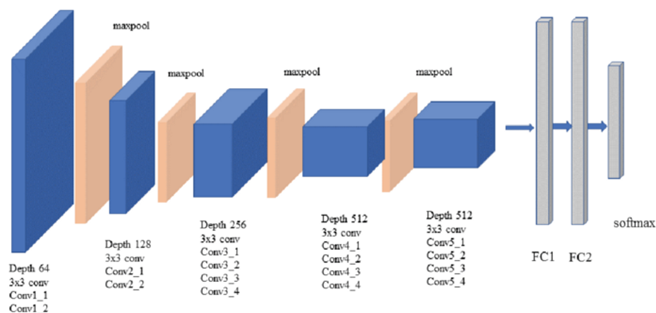

i += 1During training, the input to our VGG-19 is a fixed-size 256 × 256 gray scale image. The image is passed through a stack of convolutional (conv.) layers, where we use filters with a very small receptive field: 3 × 3 .The padding is same for 3 × 3 convolution layers.Max-pooling is performed over a 2 × 2 pixel window, with stride 2. A stack of convolutional layers is followed by three Fully-Connected (FC) layers: the first two have 1024 channels each.The final layer is the soft-max layer.. All hidden layers are equipped with the rectification (ReLU (Krizhevsky et al., 2012)) non-linearity.

The Code:

def VGG19(input_shape,filters):

inputs=tf.keras.layers.Input(shape=input_shape)

x = tf.keras.layers.Conv2D(filters//16,(3,3), activation = 'relu', padding = 'same', kernel_initializer = 'he_normal')(inputs)

x=tf.keras.layers.Dropout(0.1)(x)

x = tf.keras.layers.Conv2D(filters//16,(3,3), activation = 'relu', padding = 'same', kernel_initializer = 'he_normal')(x)

x=tf.keras.layers.BatchNormalization()(x)

x = tf.keras.layers.MaxPooling2D(pool_size=(2, 2))(x)

x = tf.keras.layers.Conv2D(filters//8,(3,3), activation = 'relu', padding = 'same', kernel_initializer = 'he_normal')(x)

x=tf.keras.layers.Dropout(0.2)(x)

x = tf.keras.layers.Conv2D(filters//8,(3,3), activation = 'relu', padding = 'same', kernel_initializer = 'he_normal')(x)

x=tf.keras.layers.BatchNormalization()(x)

x = tf.keras.layers.MaxPooling2D(pool_size=(2, 2))(x)

x = tf.keras.layers.Conv2D(filters//4,(3,3), activation = 'relu', padding = 'same', kernel_initializer = 'he_normal')(x)

x=tf.keras.layers.Dropout(0.3)(x)

x = tf.keras.layers.Conv2D(filters//4,(3,3), activation = 'relu', padding = 'same', kernel_initializer = 'he_normal')(x)

x=tf.keras.layers.BatchNormalization()(x)

x = tf.keras.layers.Conv2D(filters//4,(3,3), activation = 'relu', padding = 'same', kernel_initializer = 'he_normal')(x)

x=tf.keras.layers.BatchNormalization()(x)

x = tf.keras.layers.MaxPooling2D(pool_size=(2, 2))(x)

x = tf.keras.layers.Conv2D(filters//2,(3,3), activation = 'relu', padding = 'same', kernel_initializer = 'he_normal')(x)

x=tf.keras.layers.Dropout(0.4)(x)

x = tf.keras.layers.Conv2D(filters//2,(3,3), activation = 'relu', padding = 'same', kernel_initializer = 'he_normal')(x)

x=tf.keras.layers.BatchNormalization()(x)

x = tf.keras.layers.Conv2D(filters//2,(3,3), activation = 'relu', padding = 'same', kernel_initializer = 'he_normal')(x)

x=tf.keras.layers.BatchNormalization()(x)

x = tf.keras.layers.MaxPooling2D(pool_size=(2, 2))(x)

x = tf.keras.layers.Conv2D(filters,(3,3),activation = 'relu', padding = 'same', kernel_initializer = 'he_normal')(x)

x=tf.keras.layers.Dropout(0.5)(x)

x = tf.keras.layers.Conv2D(filters,(3,3), activation = 'relu', padding = 'same', kernel_initializer = 'he_normal')(x)

x=tf.keras.layers.BatchNormalization()(x)

last = tf.keras.layers.Conv2D(filters,(3,3), activation = 'relu', padding = 'same', kernel_initializer = 'he_normal',name='top_conv')(x)

model=tf.keras.Model(inputs,last,name="VGG19")

return modelIn fully connective layers, we will use L1-L2 regulazier to prevent overfitting .